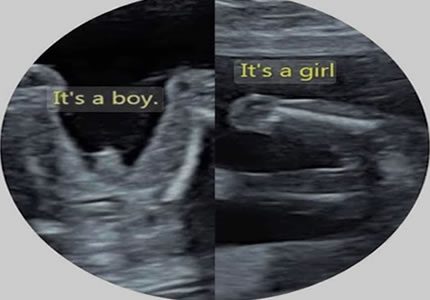

Gender & Mid-Pregnancy Scans (16 – 24 Weeks)

- Discover the sex of your baby with high-resolution imaging. While the reveal is the highlight, our sonographers always perform a professional wellbeing check, monitoring growth and heart activity, to ensure your baby is hitting their milestones.

- £69